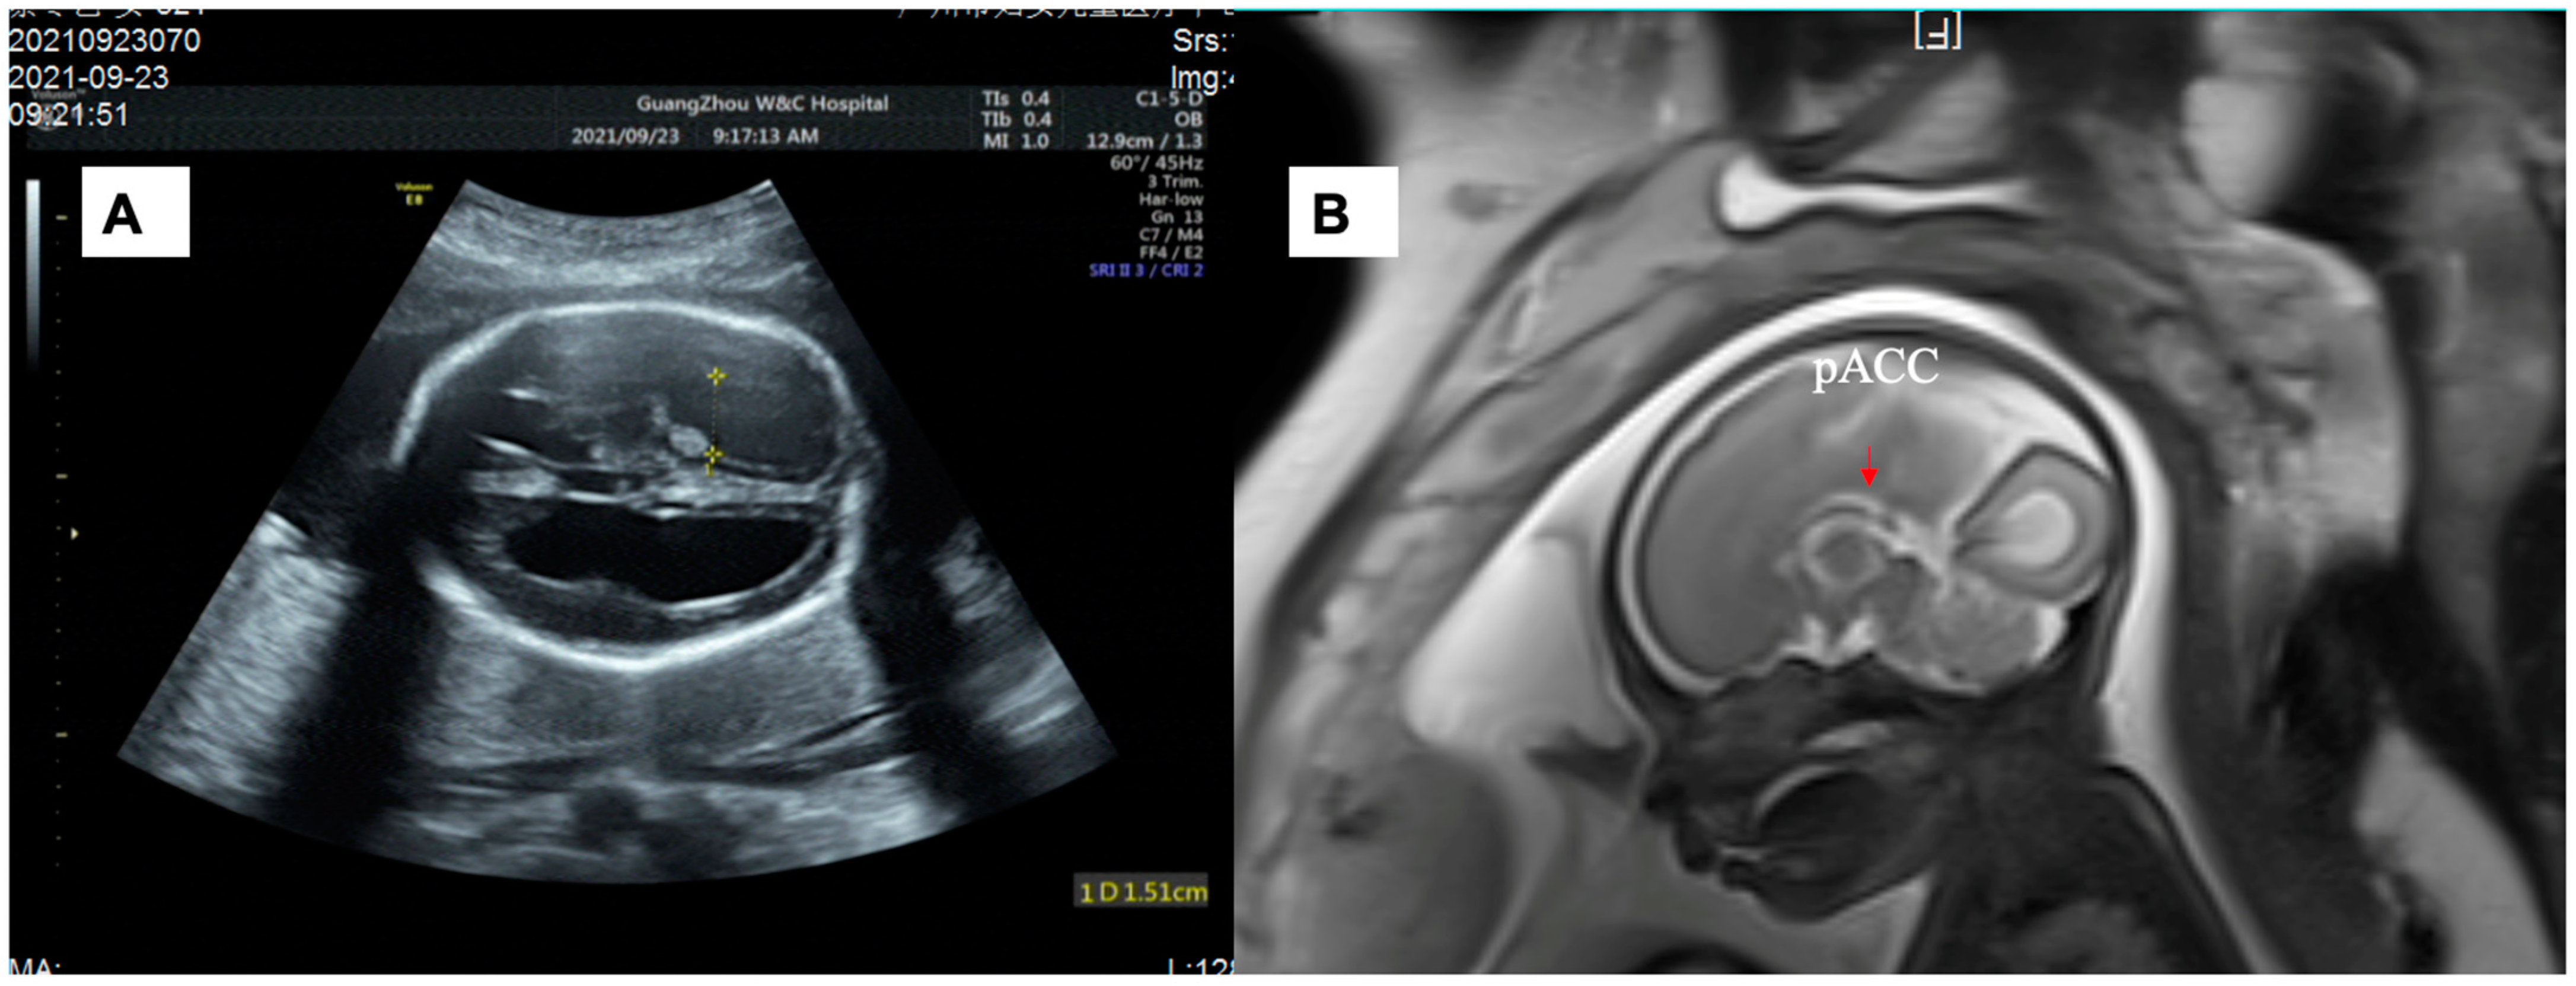

| 40 | 26+ gestation weeks, M | c.544C > T | p. R182W | partial agenesis of the corpus callosum | - | severe lateral ventriculomegaly | - | - | our study |